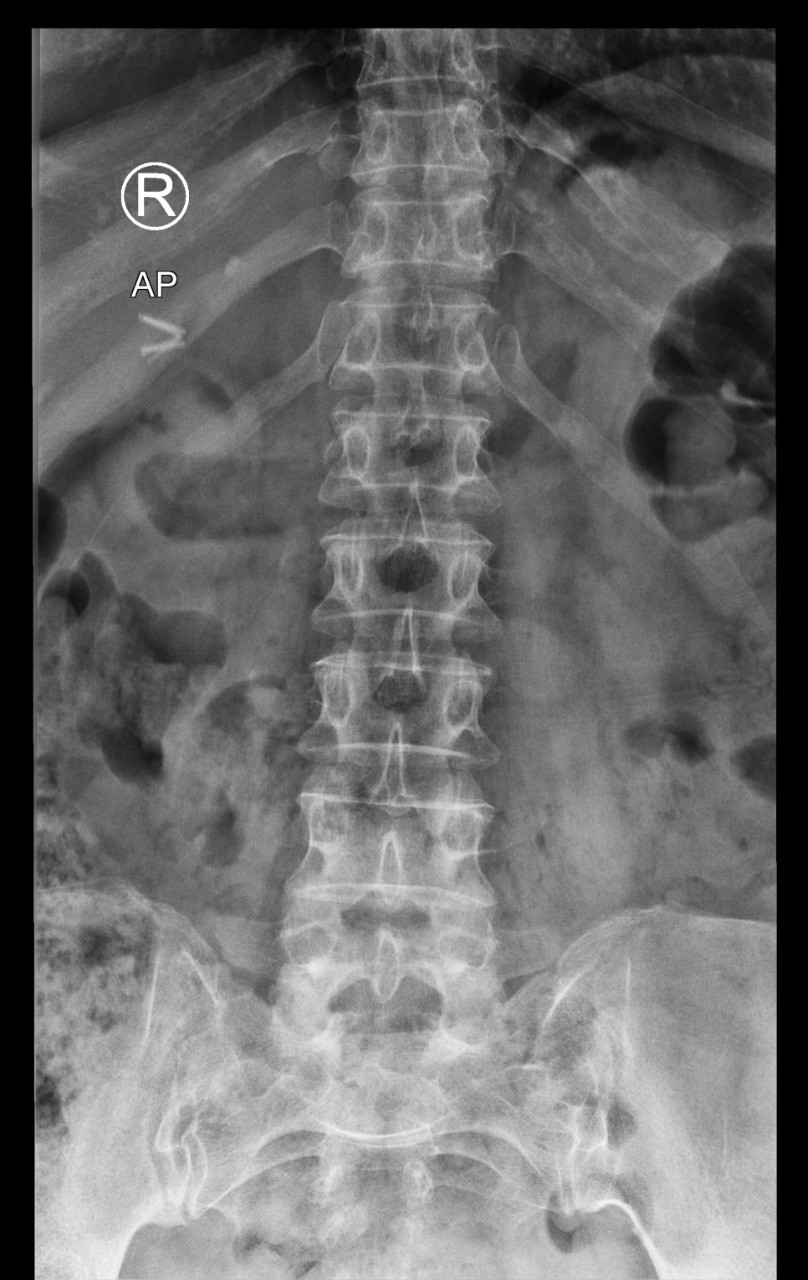

في كل يوم اسمع أمي ومن هم حولي من كبار السن يعانون من الآم مستمرة في العظام تحديدًا في منتصف الظهر والورك الأيمن والأيسر والركبتين، فهذه المناطق أرى أن أكثر كبار السن يشتكون منها. المراجعات الخاصة بالمسشتفى بلا فائدة، الأدوية كذلك. تأثرت صحة أمي كثيرًا فلم تعد تمارس اعمالها كما في السابق ولم تعد حتى تقدر على طلوع الدرج ولا الجلوس كثيرًا. وهذه بعض صور الخاصة بأشعة العظام عندما تم فحصها